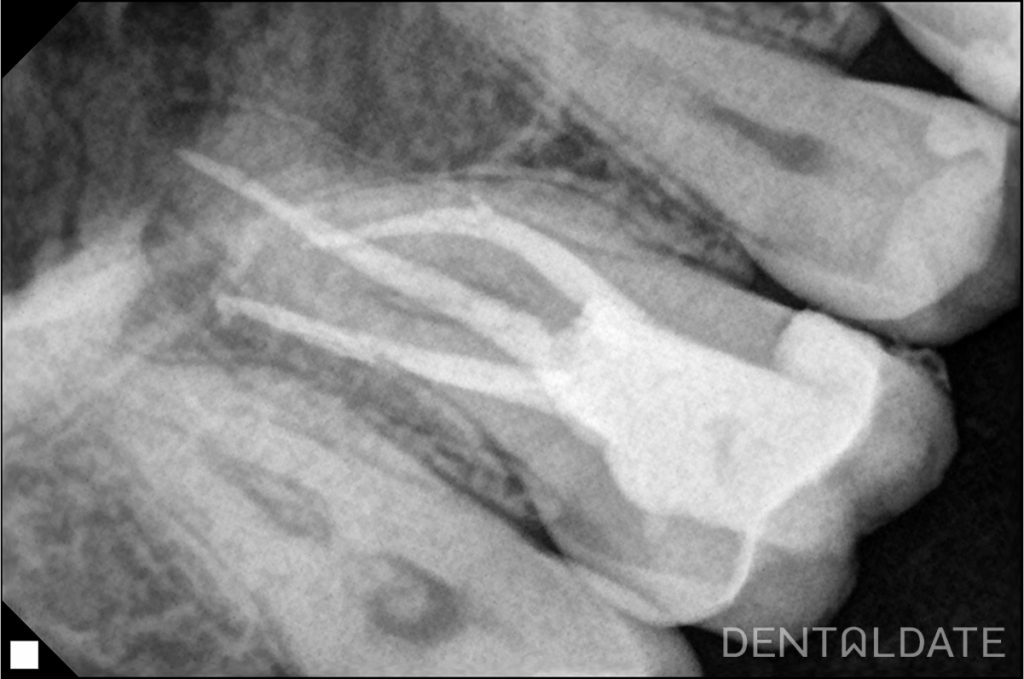

On CBCT: The tooth was previously treated endodontically in another clinic. The medial cheek root has a complex curve in the apical third. The canals are obturated to the apex. In the periapical tissues of the medial cheek root there is a focus of radiolucency, the contours are not clear.

It was decided to re-treat the canals of tooth 1.6.

The old filling was removed. Access to the root canals was created. The root canals were unsealed. Calcium hydroxide was placed in the canals for 2 weeks for the purpose of disinfection inside the root structure.

After 2 weeks the canals were mechanically and medically prepared for obturation and filled by the method of hot condensation of gutta-percha and siler AH plus. Filling.